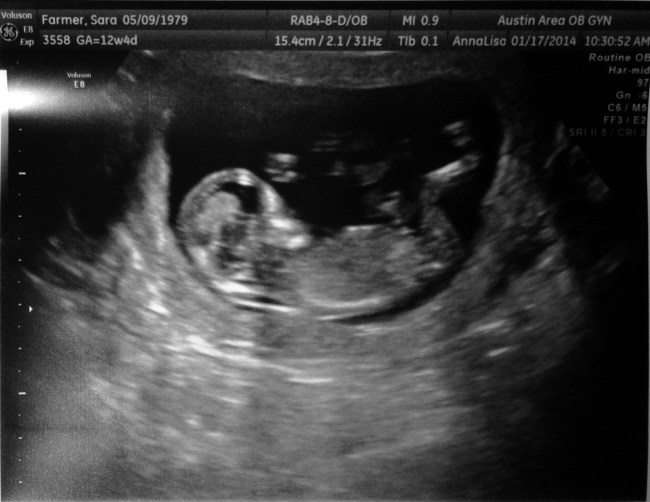

Those clinical, carefully ambiguous words filled me with incredulous joy. It’s a GIRL, folks! A healthy girl!! She is still too small for us to get a good look at her heart, but we have successfully cleared another hurdle. She is still alive and chromosomally normal at 15 weeks!

The test is incredibly accurate, though. The last ultrasound tech said she was 80% sure it’s a girl. I’ve had a gut feeling it was a girl for most of the pregnancy. (My gut has not been wrong yet, as far as I know. We never got to find out with Baby Bean.) The nurse at the doctor’s office said she calls it, “The 100% test”.